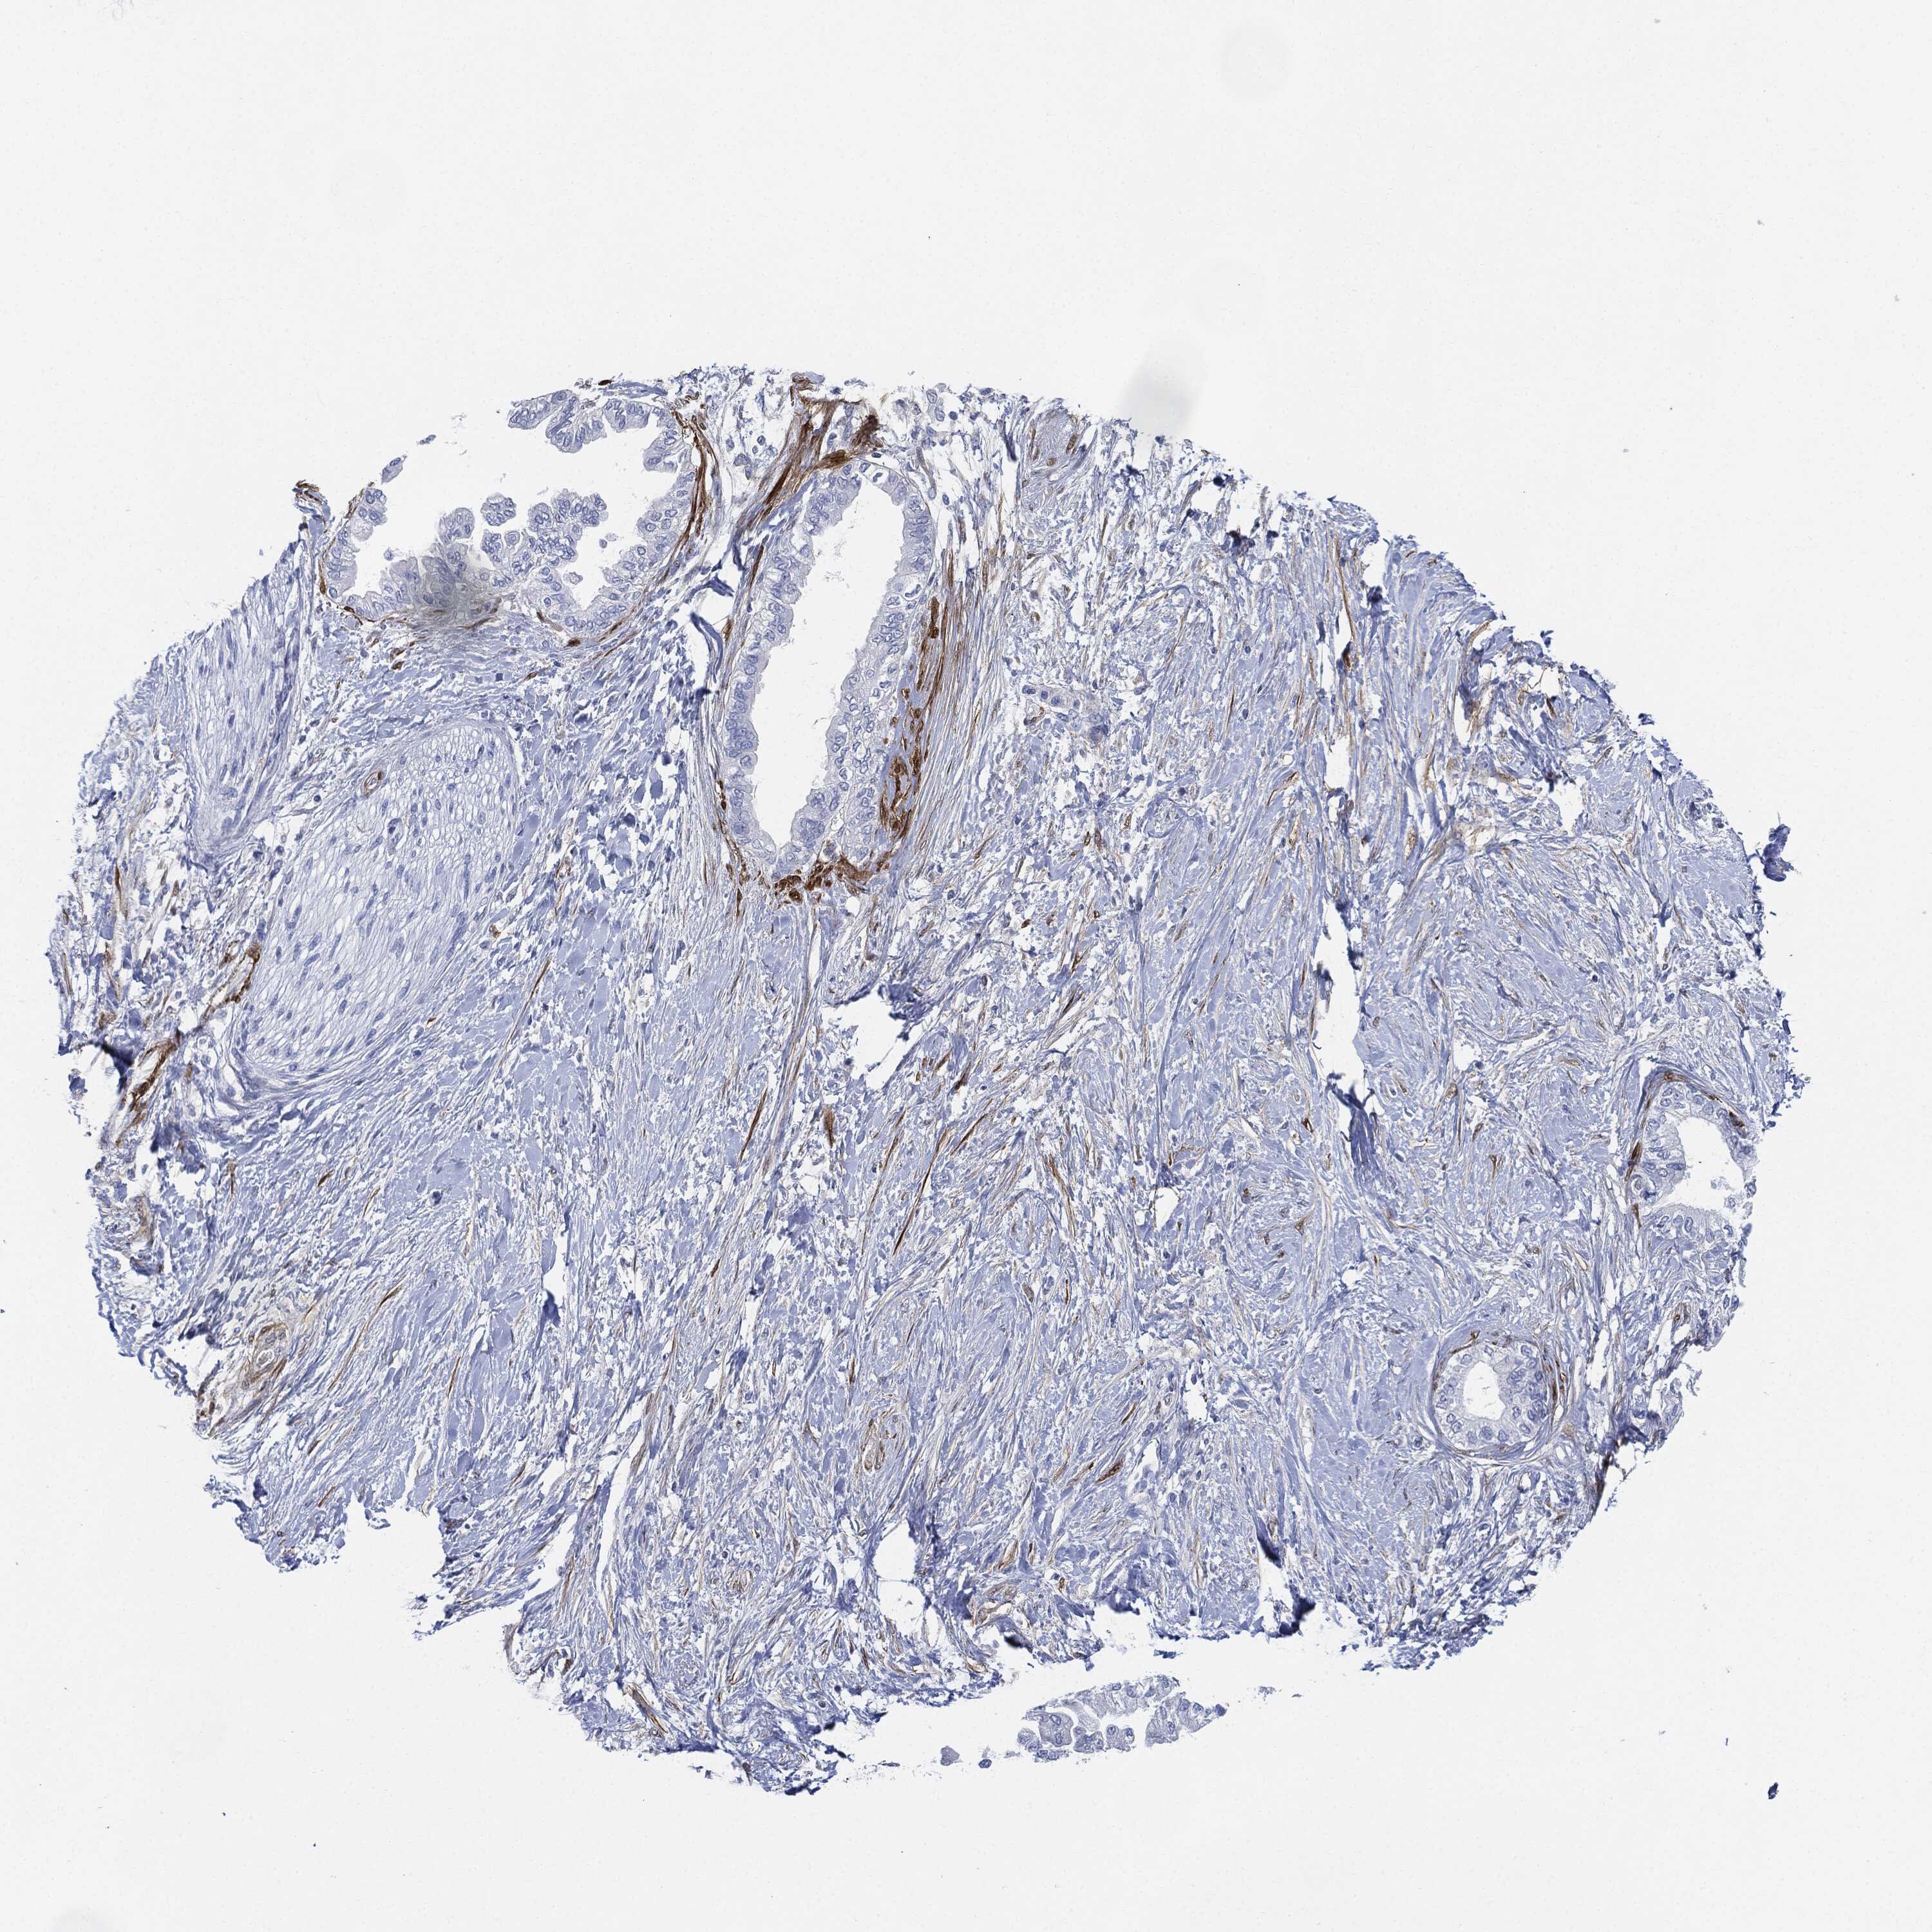

PANCREATIC CANCER - Protein expressioni

A mouse-over function shows sample information and annotation data. Click on an image to view it in a full screen mode. Samples can be filtered based on level of antibody staining by selecting one or several of the following categories: high, medium, low and not detected. The assay and annotation is described here.

Note that samples used for immunohistochemistry by the Human Protein Atlas do not correspond to samples in the TCGA dataset.

Antibody stainingi

Antibody staining in the annotated cell types in the current human tissue is reported as not detected, low, medium, or high, based on conventional immunohistochemistry profiling in selected tissues. This score is based on the combination of the staining intensity and fraction of stained cells.

Each image is clickable and will lead to virtual microscopy that enables deeper exploration of all samples and also displays staining intensity scores, fraction scores and subcellular localization as well as patient and tissue information for each sample.

Antibody HPA019467

Antibody HPA061657

Antibody CAB001447

Staining

High

Medium

Low

Not detected

Intensity

Strong

Moderate

Weak

Negative

Quantity

>75%

75%-25%

<25%

None

Location

Nuclear

Cytoplasmic/membranous

Cytoplasmic/membranous,nuclear

Adenocarcinoma, NOS